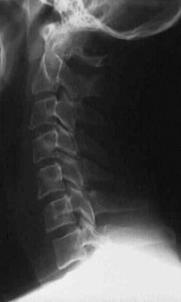

TRAUMA CERVICALA

Incidenta laterala Incidenta

laterala Incidenta

Aspect normal Imagine

incompleta Aspect

normal

Incidenta oblica Incidenta laterala Incidenta antero-posterioara

Aspect normal Aspect normal Aspect normal